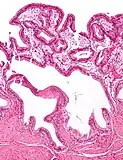

Micrograph of cholesterolosis of the gallbladder, with an annotated foam cell. H&E stain.

The name strawberry gallbladder comes from the typically stippled appearance of the mucosal surface on gross examination, which resembles a strawberry. Cholesterolosis results from abnormal deposits of cholesterol esters in macrophages within the lamina propria (foam cells) and in mucosal epithelium. The gallbladder may be affected in a patchy localized form or in a diffuse form. The diffuse form macroscopically appears as a bright red mucosa with yellow mottling (due to lipid), hence the term strawberry gallbladder. It is not tied to cholelithiasis (gallstones) or cholecystitis (inflammation of the gallbladder).[2]